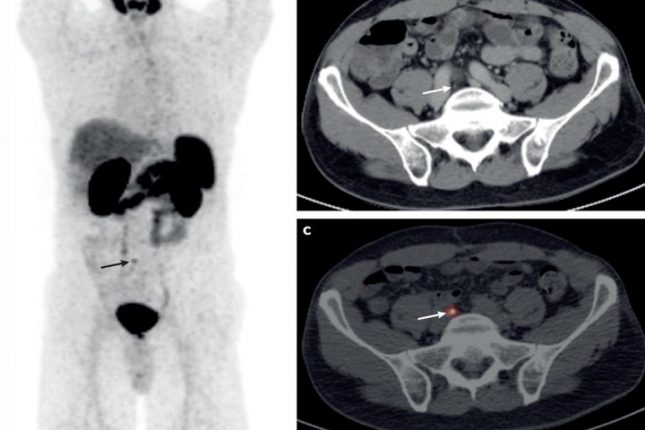

Hoy Aragón entrevista a Alberto Jiménez Schuhmacher, IP el Grupo de Oncología Molecular del IIS Aragón, donde está desarrollando una técnica de diagnóstico del cáncer bautizada como ‘biopsia virtual’ y otra técnica de cirugía guiada por fluorescencia. Su meta es conseguir un diagnóstico más eficaz y menos invasivo del tumor cerebral más letal, el cáncer de páncreas y ciertos tumores infantiles.